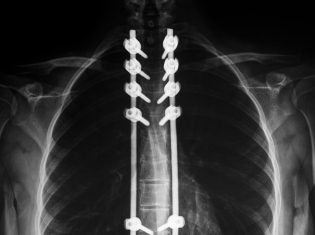

Modern implantaat bij rugartrose niet beter dan klassieke operatie

Symptomen van artrose in de rug zijn te bestrijden met een implantaat of met een grotere operatie. Gedacht werd dat patiënten die een implantaat...